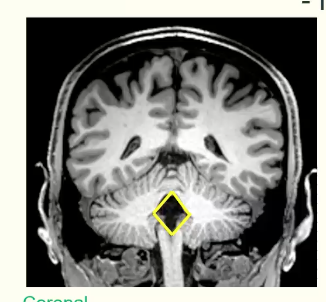

In a coronal view of the fourth ventricles, what is the shape?

Rhomboid (diamond) shape of fourth ventricles